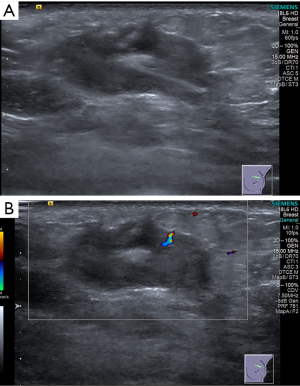

Mammography of the breast showed a partially obscured mass with some margins visible (approximately 2.0 cm × 1.7 cm) (Figure 1). The patient also underwent an ultrasound examination, which revealed a hypoechoic, heterogeneous solid mass with indistinct borders measuring approximately 30 mm × 13 mm × 20 mm. The mass was located at the 12 o’clock position, approximately 4 cm from the left nipple, and involved the subcutaneous layer (Figure 2A). According to the Breast Imaging Reporting and Data System (BI-RADS) classification, this lesion is considered to be in the 4C category (12). Color Doppler ultrasound showed blood supply within the mass (Figure 2B). Multiple solid nodules were observed in the remaining areas of both breasts (BI-RADS category 3).

Figure 2 Two-dimensional and color Doppler ultrasound images of mass. (A) Left breast features a hypoechoic mass approximately 30 mm × 13 mm × 20 mm in size at the 12 o’clock position, with unclear borders and irregular shape. The internal echogenicity of the mass is heterogeneous, with only slight hypoechogenicity visible. (B) Color Doppler ultrasound displays a prominent thick vessel within the tumor.